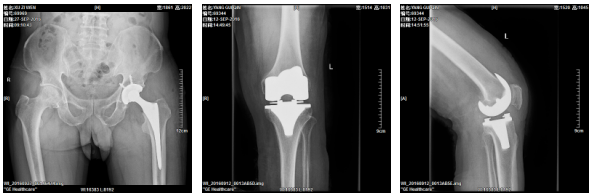

2、髋关节全髋、半髋置换手术、膝关节表面置换手术、关节融合手术。

技术专长:髋关节置换、膝关节置换、脊柱内固定、关节镜微创技术。